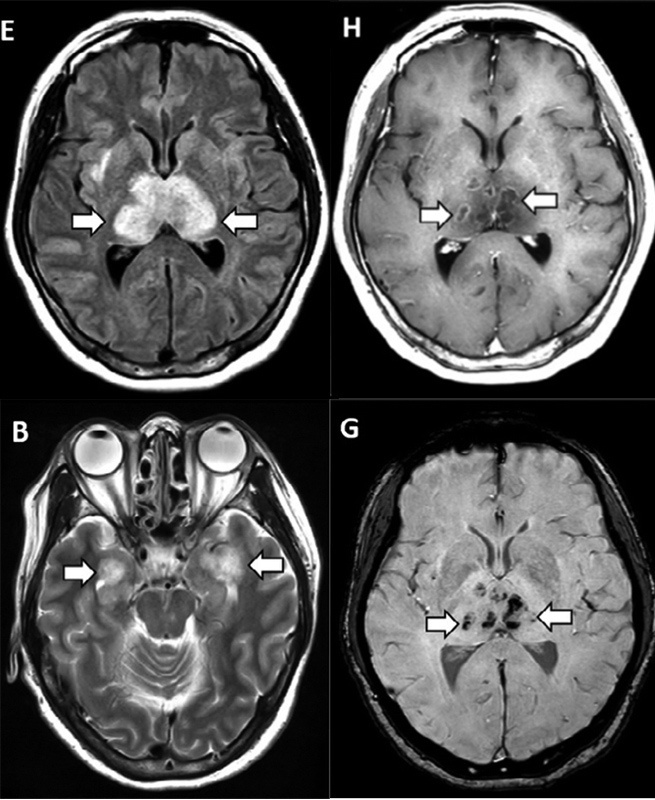

Ей провели компьютерную томографию без контраста, КТ-ангио- и венографию (с введением контрастного вещества), а также магнитно-резонансную томографию с контрастированием. Со стороны сосудов головного мозга никаких изменений не наблюдалось, чего нельзя было сказать про мозговое вещество.

И на КТ, и на МРТ было выявлено симметричное поражение таламусов, на МРТ также обнаружили поражение медиальных отделов височных долей и субостровковых областей. При введении контрастного вещества наблюдалось его кольцевидное накопление, что говорило о нарушении в местах поражения мозговой ткани гемато-энцефалического берьера. Причем, в этих же местах обнаруживались мелкие кровоизлияния.

МРТ головного мозга пациентки. На снимках стрелочками показаны поражения талмудов (Е), медиальных отделов височных долей (B), кровоизлияния (черные точки, G) и кольцевидное накопление контрастного препарата (кольцевидные светлые участки, Н). Credit: Brent Griffith et al. / Radiology 2020